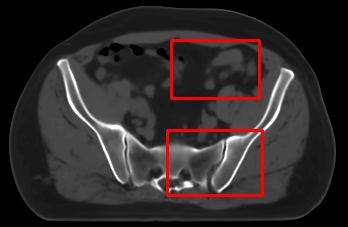

In the MRI CT translation in the Gold Atlas dataset (Fig. 8), major bones and muscles are translated faithfully. Yet, diffusion sampling leads to some inaccuracies in the outline of bones and hallucinations of the textures of inner organs. Conversely, regression sampling faithfully translates bones while still blurring the inner organs and generating artifacts. This indicates that rendering CTs is under-defined by the given MRI guidance alone.

In the quantitative analysis (Tab. 3), we found a slightly increased performance of sampling with over regression sampling in terms of PSNR and accuracy of the downstream task. As performance gains are marginal and the assessment is based on few () test cases, we still assume the performance of diffusion and regression to be similar.

Diffusion sampling YODA results in hallucinated organ shapes and textures that smoothen out and disappear when increasing the in Exp sampling or when using regression sampling. Regression sampling creates some artifacts. Note that, for all methods, the translation quality for inner organs is rather poor, whereas bone and muscle translation is reliable.

When benchmarking on the more heterogeneous and lower-quality BraTS dataset (Tab. 2, left), regression sampling of YODA achieved significantly better images than all competing methods in terms of PSNR, SSIM, and downstream glioma segmentation. Similar results were obtained in the IXI dataset (Tab. 2, right), where YODA significantly outperformed all competing methods in SSIM and PSNR. In the full-brain segmentation conducted from the synthetic images, YODA’s images were significantly better than all competing methods in at least either the Dice score or the HD. In the MRI CT task on the small pelvic dataset, regression and ExpA sampling achieved the highest SSIM, whereas the DB of Choo et al. [31] had the highest PSNR. Both, regression and ExpA sampling YODA also performed competitively in the downstream segmentation task. Note that, for all methods, the translation of inner organs was rather poor and included either texture hallucination (ResViT, I2I-Mamba, diffusion-sampling YODA) or an over-smooth image appearance (Choo et al. [31], SelfRDB, SynDiff, ExpA and regression sampling YODA, Fig. 8).